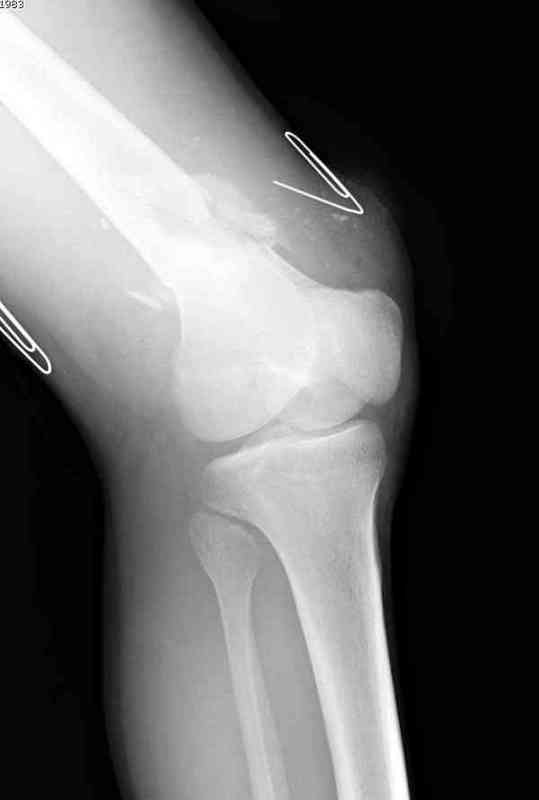

Пострадавшему 23, пистолетная огнестрельная не кроветочащая рана, меньше одного см диаметром, входное отверстие расположено латерально, и выход передне-медиально, и еще имеется второе пулевое ранение правой navicular bone с этой стороны.

Несмотря на сниженный до 0.9 BI-ankle-brachial-index (обязательное, недорогое исследование при подозрении на повреждение сосудов, рассчитанный по разнице давления в нижней и верхней конечности), последующее КТ ангиограмма не подтвердила повреждения артериальных сосудов.

Доступ был латеральный, при вскрытии с задней

поверхности бедра обнаружили кровотечение. Поднятием давления на заранее установленном турникете на конечности проконтролировали кровотечение.

В данном случае мы не ставили осуществление гемостаза приоритетным, после 30 минут больной оставлен вызванному сосудистому хирургу со стабильной фиксацией бедра. Несмотря на выбранный передне-медиальный доступ, хирург произвел восстановление сосудистого повреждения.

При близости сосудов к многооскольчатому повреждению костей, сперва необходимо удостовериться в наличии повреждения сосудов без применения турникета.

Сосудистые повреждения часто приводят к увеличению

давления в компартментах, мониторинг на голени показал увеличение, и поэтому сделана профилактическая латеральная фасциотомия.

Латерально пластину защитили ушиванием

илио-тибиального тракта, а медиальная сторона была ушита мышцей, и все раны закрыли ваккумированием (VAC)

На третий день после Irrigation & Debridment закрыли все раны за исключением компартментальной раны из-за отека, медиально в дефект кости установили Putty Grafton Bone Substitute. На компартментальную рану вакуум и мероприятия по сближению краев раны резиновой стяжкой.

На 9й день с момента травмы ушили рану без натяжения. Больной получает реабилитацию, движения коленного сустава с помощи CPM-continuous passive motion machine. Сегодня выписан.